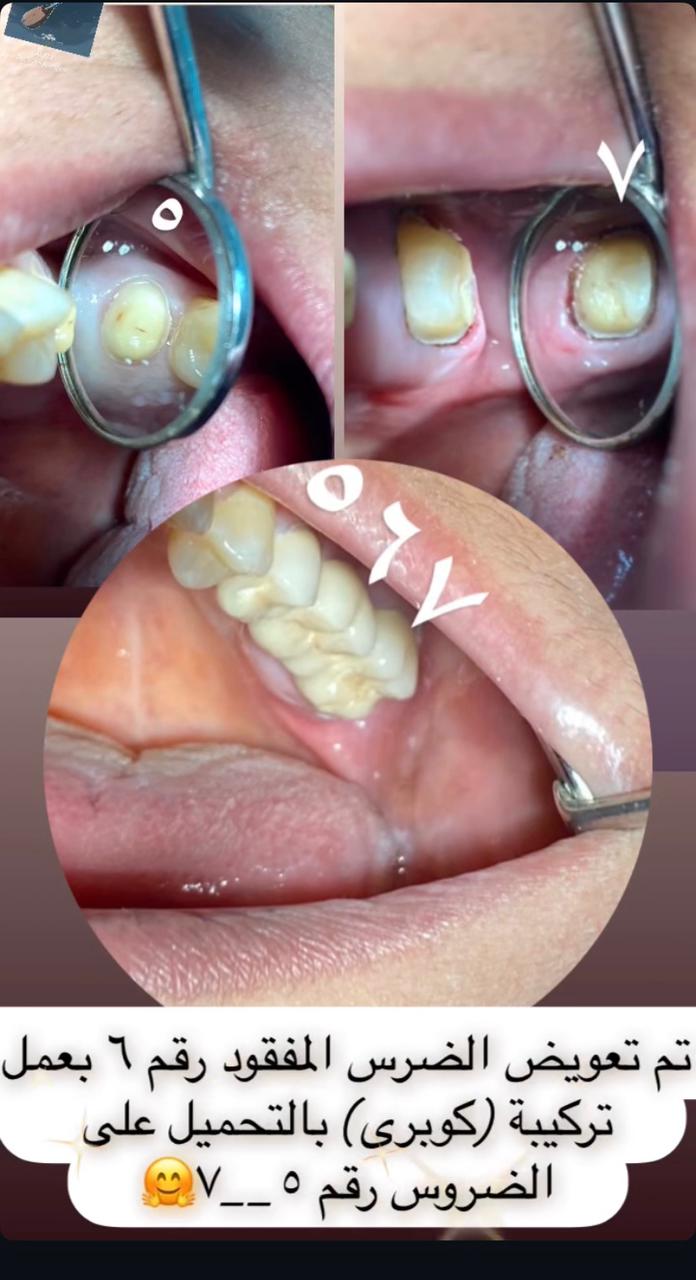

تركيبات الأسنان الثابتة

جراحة الأسنان